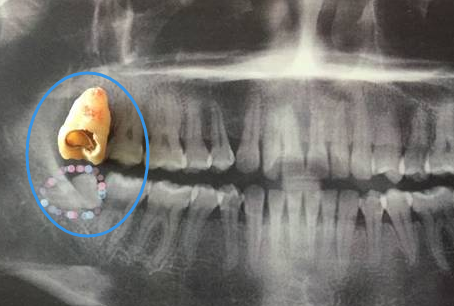

智齒蛀牙拔牙

比較常見的是智齒位置不正,各種長歪,然後自身蛀牙,以及引起鄰牙蛀牙,這種情況的話,是建議直接拔除的,不需要繼續保留的,因為(wei) 智齒本身在口腔內(nei) 是沒有牙齒功能的,如果是正畸牽引智齒可以繼續使用,這是比較好的方法。

如果是智齒自身蛀牙,還造成鄰牙也蛀牙的,是需要及時拔除智齒後,並補牙治療鄰牙,這樣可以保障鄰牙可以繼續使用。